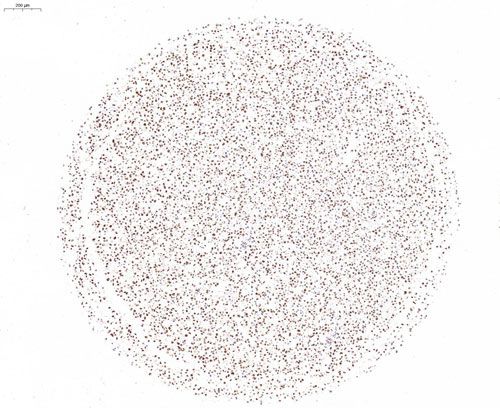

H腫瘤細胞芯片-PCNA

H腫瘤細胞-PCNA染色